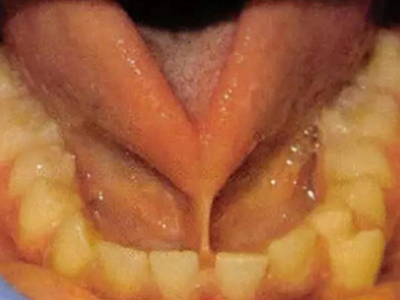

舌系带过短多见于儿童,张口时,舌体挛缩,可暴露舌系带。伸舌时,舌不能自然伸至下唇外侧,用力伸舌时舌尖呈“V”字形或“W”型凹陷。语言障碍患者不能发出舌腭音及卷舌音,发音吐字不清。舌系带过短的幼儿哺乳时,由于舌前伸时系带与下前牙切端摩擦,易形成溃疡、疼痛,导致哺乳障碍。

舌系带过短是一种先天发育异常,由于舌系带在舌腹部的附着点前移至舌尖或接近舌尖,或牙槽嵴附着点上移至牙槽嵴上部,或者附着点正常,系带本身过短可引起该症状。